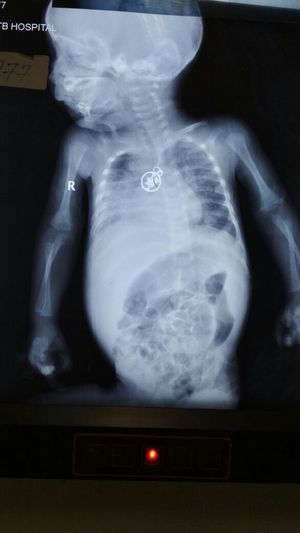

Foreign body

Foreign body in food pipe??

Lateral view is needed for judging whether it is in food pipe or airway..